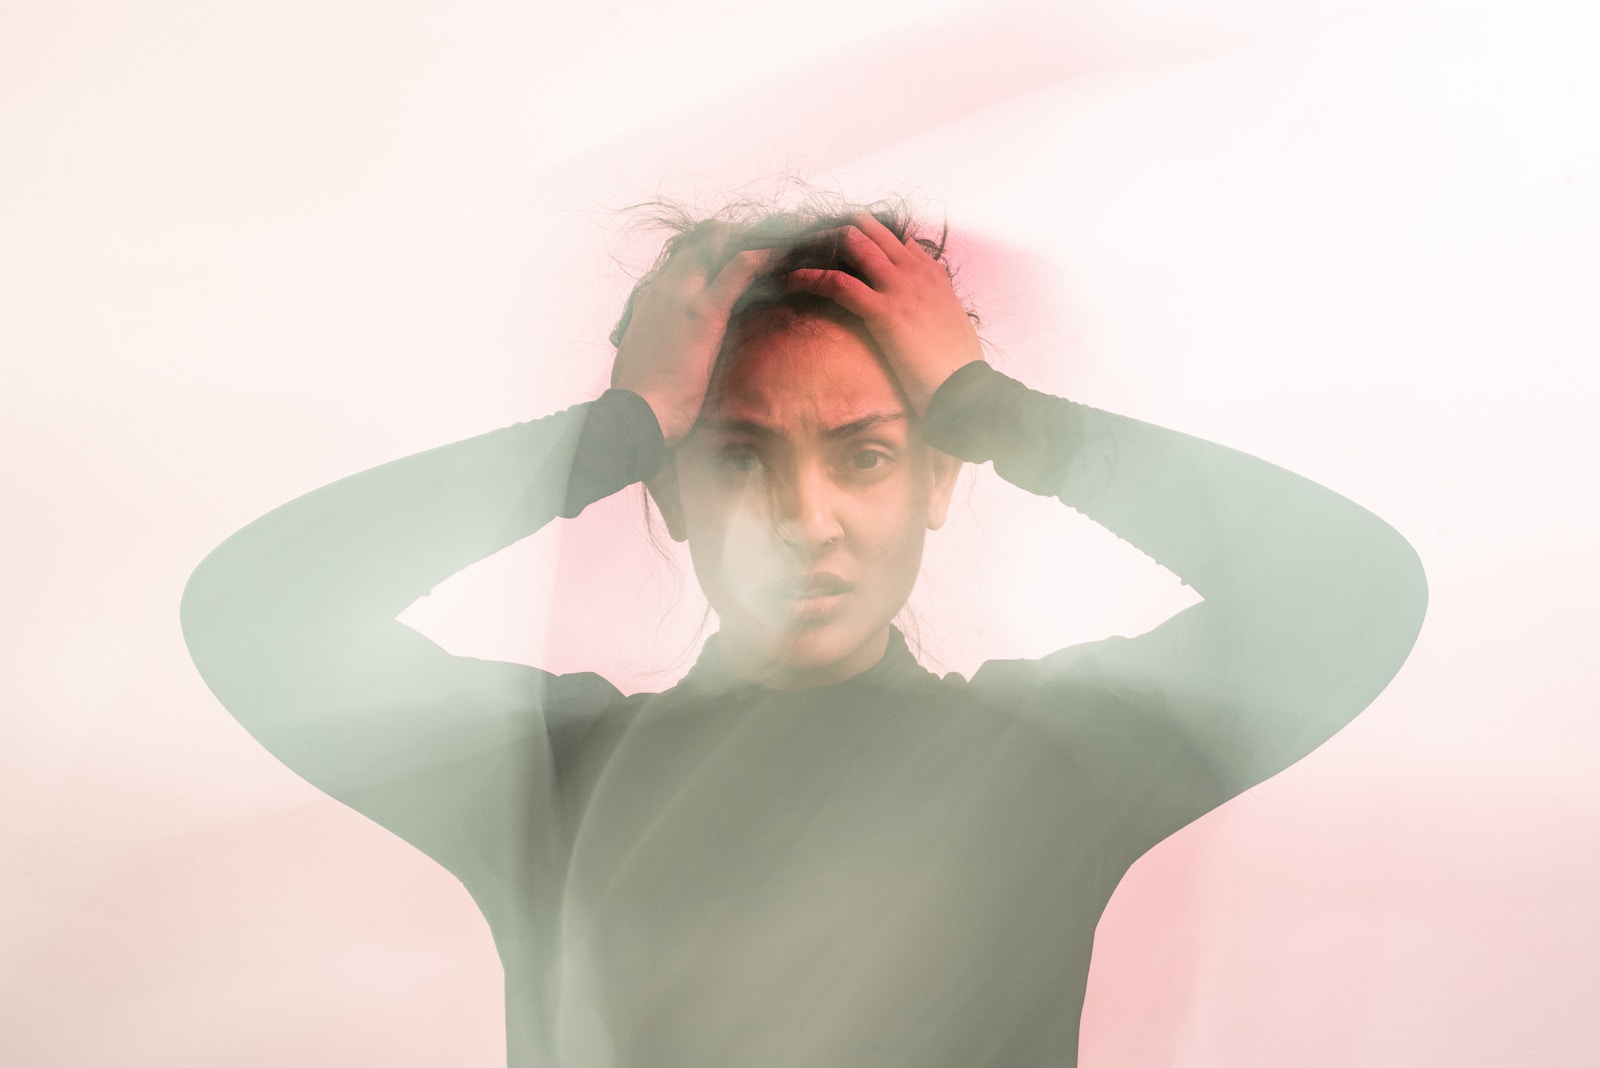

Máte strach z verejných priestorov plných ľudí? Možno trpíte agorafóbiou.

Agorafóbia je psychická porucha z radu úzkostných, o ktorej ste už určite počuli. Osoba, ktorá trpí touto poruchou má strach z verejných priestranstiev – zo situácii ako ulica, obchod či MHD plná ľudí. Možno sa to niekomu bude zdať nelogické, absurdné alebo hlúpe, no pravdou je, že táto fóbia patrí k najčastejšie sa vyskytujúcim v populácií ľudí.

Ide o fóbiu, ktorá má korene už v starovekom Grécku. Jej príznaky a priebeh sa líšia od človeka k človeku, no okrem úzkosti sú typické aj panické ataky, ku ktorým dochádza, keď je tento človek vystavený vonkajšiemu prostrediu. Problémy sa môžu objavovať stále častejšie, až to môže vyústiť do strachu opustiť priestory domova.

Niekto by si mohol myslieť, že na to, aby sa objavila, človek musí utrpieť nejakú duševnú traumu, no nie je to tak. Môže začať zdanlivo bezdôvodne, často medzi 25. a 35. rokom života (je však aj veľa prípadov, kedy sa objavila omnoho skôr). Jednoducho, jedného dňa budeš prechádzať ulicou, keď ťa zrazu prepadne panika, ktorá sa bude neustále stupňovať. Toto bude pokračovať a zhoršovať sa rôznymi úzkostnými myšlienkami.

Neustále sa cítite ohrozený

Agorafóbia sa okrem strachu z vonkajších priestorov spája so strachom ako takým. Aj celkom obyčajné a bežné veci, nad ktorými sa iný ľudia ani len nepozastavia agorafobikom prinášajú strach a pot na tvári. Máte problém ísť von, rozprávať sa s ľuďmi, plniť si povinnosti, máte obavy o seba, svoju rodinu i priateľov.

Ľahko sa ocitnete v bludnom kruhu

Zjednodušene povedané, ide o strach zo strachu. Prežiť panický atak nie je pre nikoho príjemné. Agorafobik, ktorý ho zažije čo i len jeden jediný krát začne mať strach z toho, že sa zopakuje. Kvôli tomu, prestane chodiť von, aby čo najviac minimalizoval možnosť, že k nemu dôjde. Týmto prístupom sa však len dostáva do bludného kruhu, z ktorého je ťažké dostať sa von.